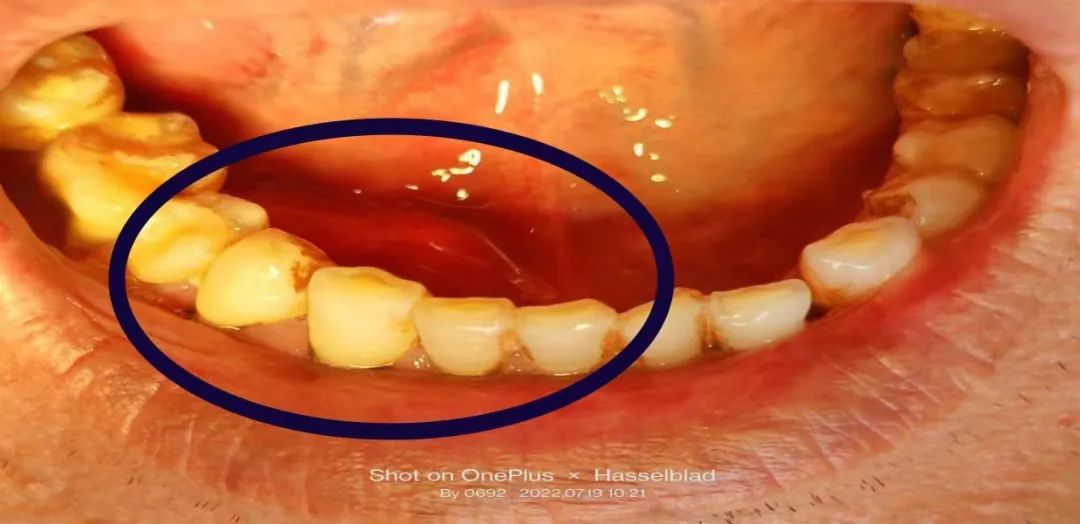

患者口内颌下腺导管结石术前照片

做好术前准备后,薛主任在门诊手术室,局部浸润麻醉下进行下颌下腺导管内结石取出手术。手术过程中,手术创口较小,创口出血较少,患者配合程度较高,手术用时较短,薛主任以最优的手术方案成功取出患者口内下颌下腺导管口内长约18mm、宽约16mm巨大结石。为患者提供了对身体损伤最小,创口最优,花钱最少的处理方案,以最快的时间解决了患者的病痛。